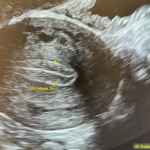

Dar, după multe discuții, vor să mai încerce o dată cu ovocitele doamnei!! Ce pot să vă spun? 5 ovocite, 1 blastocist ziua 6, testat euploid, beta-hCG pozitiv!!😮😍